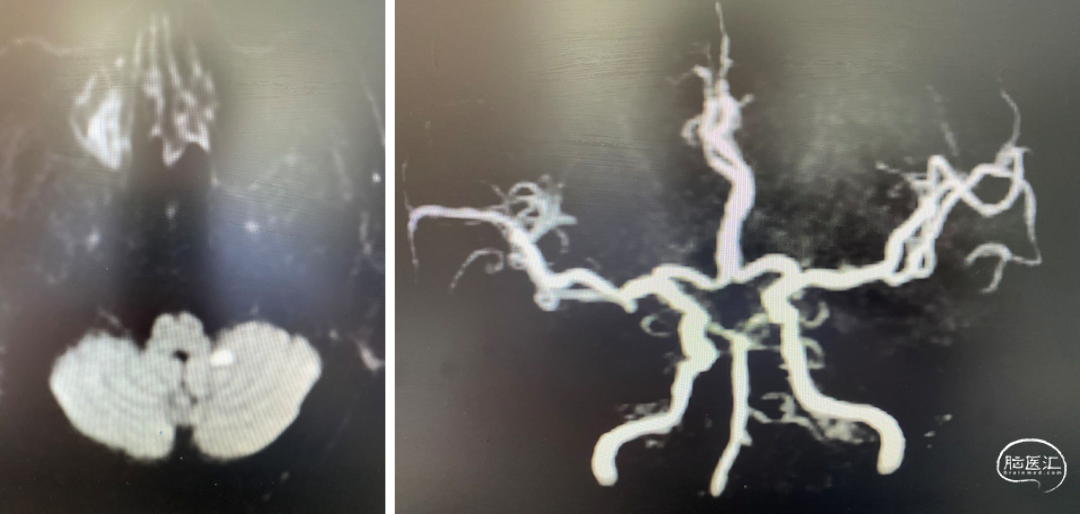

颅脑DWI+MRA:

重要影像结论:后循环供血区多发梗死灶,后循环血管显影不良。

重要影像结论:桥脑新发亚急性梗死灶,右侧椎动脉重度狭窄。